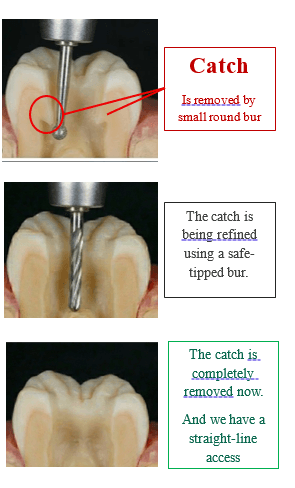

Definition: “Catches” are irregularities in walls where instruments get stuck.

Risk: Causes ledging or perforation.

Action: Use a round bur to smoothen internal walls (un-roofing the chamber). Verify smoothness with a fine endodontic explorer.